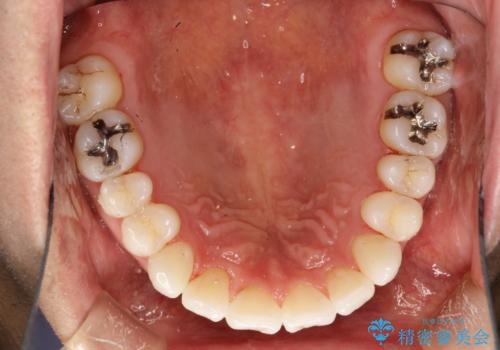

インビザライン終了時のPMTC

- インビザライン治療が終了し、アタッチメント除去の際にクリーニング(PMTC)も希望されました。

PMTC60分1万円+tax(保険適応外)を行いました。

インビザライン矯正治療は、歯にアタッチメント(歯を動かすための突起物)をつけます。そのため、矯正治療が終了し、アタッチメントを外すと着色が目立つことがあります。矯正治療の終了のタイミングではクリーニングを行い、着色の除去や歯と歯の間・歯と歯肉との境目などのケアをしっかりすることをおすすめしています。